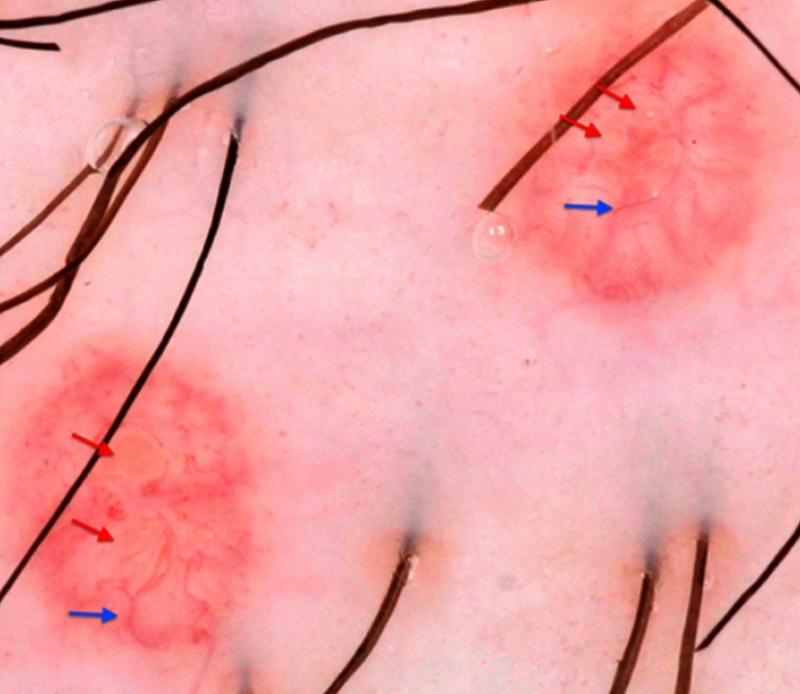

Achados dermatoscópicos do molusco contagioso. As setas vermelhas indicam estruturas polilobulares brancas a amarelas; setas azuis: vasos de coroa. (Dermoscopia com luz polarizada, ampliação original 10x)

Clinical, Cosmetic and Investigational Dermatology 2019:12 373-381. Originalmente publicado por e usado com permissão de Dove Medical Press Ltd.